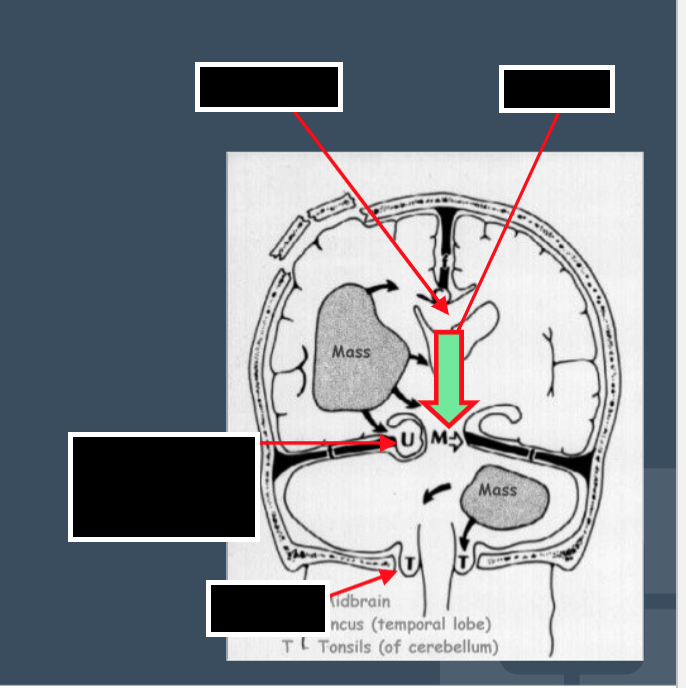

Identify the type of herniation indicated on the provided image: